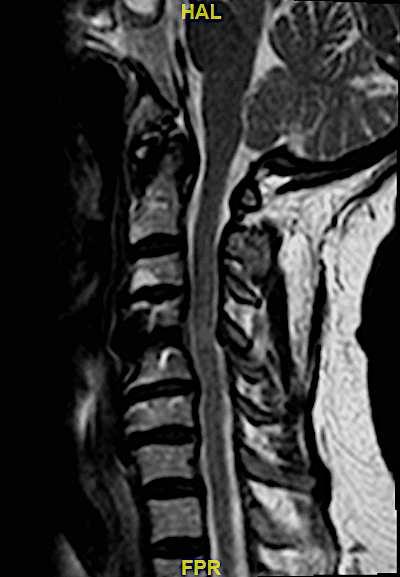

RM postoperatoria: se ha corregido la compresión anterior y posterior (de manera indirecta)